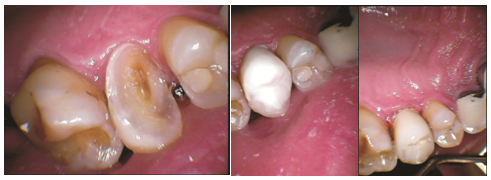

Zirconia-reinforced glass-ionomer has been successfully utilized as bioactive core restoration (Figure 1) in short-time observation in adult patient of active caries disease. Microscopic observation confirmed fine submicronic grain structure of glass particles with nano sized ceramic crystals (Figure 2). Glassy-depleted zirconia ceramics based on a polycrystalline milky zirconia powder, called 'ceramic steel', is a clue of modern restorative dentistry. Its mechanical properties and physical parameters: bending strength (840-1400MPa), modulus of elasticity (200GPa), stress intensity factor 9-10 MPa/m, Vickers hardness (13GPa), compressive strength (2,100MPa), Tensile strength (650 MPa), fatigue strength (900 MPa), fracture toughness (9 MPa/m1/2) inspire admiration as they are close to or even exceed the metal alloys. To stabilize the tetragonal metastable polycrystalline structure during thermo-dependent transformation the homogenously distributed cerium, yttrium, aluminum, magnesium or calcium oxides are added to prevent material aging by spontaneous and unwanted transformation of the TM into a monoclinic phase (up to 25%) by reacting water with oxygen-zirconium chains at the temperature of the human body, moist environment of the mouth, spongy bone and under the influence of mechanical stress. Aging zirconia may result in a loss of up to 50% of the original strength values and an increase in the volume of 3-5%, which may paradoxically compensate for the propagation of potential cracks generated in the material by auto repair. Fully stabilized cubic zirconia (FSZ) is produced with the participation of oxides: 7.9% by weight of CaO or 5.86 by weight of MgO or 13.75 by weight of Y2O3; each smaller contribution leads to a partially stabilized zirconia (PSZ) called tetragonal polycrystalline zirconia, most often with yttrium trioxide (YTZP). Tetragonal polycrystalline zirconium doped with 3-5% by weight is commonly used.34

Figure 1 a) Tooth 25, patient FK, deep caries lesion; b) fresh after bioactive restore; c) after 12 weeks.